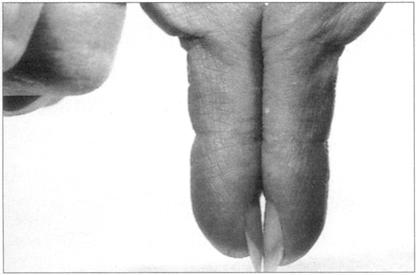

同心血管系统检查相似,呼吸系统习惯上也从检查双手开始,病人以45°头高位躺在床上。寻找杵状指,即指甲在两个方向上弯曲度增加,失去了正常的指甲角。这是由于甲床和指尖的软组织增生引起。有时指甲变化很小不易发现,在这种情况下,可以寻找钻石征(菱形征)(见图64),正常人双手指甲相对,两指甲根部之间可观察到一个小的菱形裂隙。杵状指由于指甲角丧失无法看到该裂隙。杵状指的病因很多,这里不重复了,但记得较常见于支气管癌、慢性脓胸、纤维性肺泡炎。我们也要寻找二氧化碳潴留的体征——跳跃性脉和外周静脉扩张引起的双手变暖。让患者伸出双手寻找扑动性震颤——即双手不规则的抽搐运动。二氧化碳高于正常水平会引起外周发绀。

图64 菱形征:在正常的个体当中,在指甲反折处可见菱形,如果患者的手指是棒状的,这种表现将更明显

图65 在纤维性肺泡炎中可见杵状指和外周性苍白病